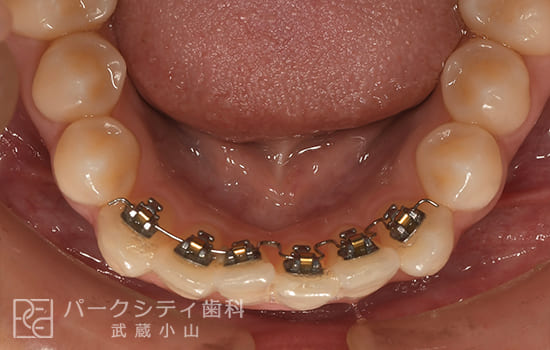

CASE.02

表側の部分矯正の症例

術前

術中1か月

術中3か月

4か月

- 主訴

- 前歯の隙間が気になる

- 治療法

- 表側の部分矯正

- 治療期間

- 4か月

- 費用

- ¥413,600

【内訳】

検査料:¥33,000

装置料:¥165,000×2(上下)

チェック:¥4,400×4

保定装置:¥16,500×2(上下)

上下表側に装置をつけ、隙間を閉じながら歯並びを整えて、約4か月で保定へ移行しました。